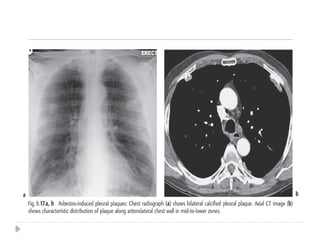

Pleural Plaques

serve as a biomarker of asbestos exposure

 The latency period between exposure to asbestos and

 The plaques involve mainly the posterior and

anterolateral aspects of the pleura, following the contours

of the posterolateral seventh to 10th ribs, and the domes

of the hemidiaphragms, and spare the lung apices and

costophrenic angles

 They almost always involve only the parietal

pleura but occasionally may be seen in the

visceral pleura in the interlobar fissures and

sometimes involve the pericardium

 On chest radiographs, pleural plaques are

unilateral in approximately 25% of cases

 more plaques are detected on CT than chest

 Pleural plaquesare circumscribed collections of dense collagenous connective tissue, which may or may not be calcified,  They represent the most common manifestation of and serve as a biomarker of asbestos exposure  The latency period between exposure to asbestos and development of pleural plaques is approximately 15 years.  The plaques involve mainly the posterior and anterolateral aspects of the pleura, following the contours of the posterolateral seventh to 10th ribs, and the domes of the hemidiaphragms, and spare the lung apices and costophrenic angles 

 They almostalways involve only the parietal pleura but occasionally may be seen in the visceral pleura in the interlobar fissures and sometimes involve the pericardium  On chest radiographs, pleural plaques are unilateral in approximately 25% of cases  more plaques are detected on CT than chest radiography.